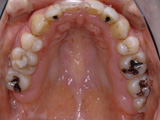

症例4:上顎前突(出っ歯)

治療前

治療後